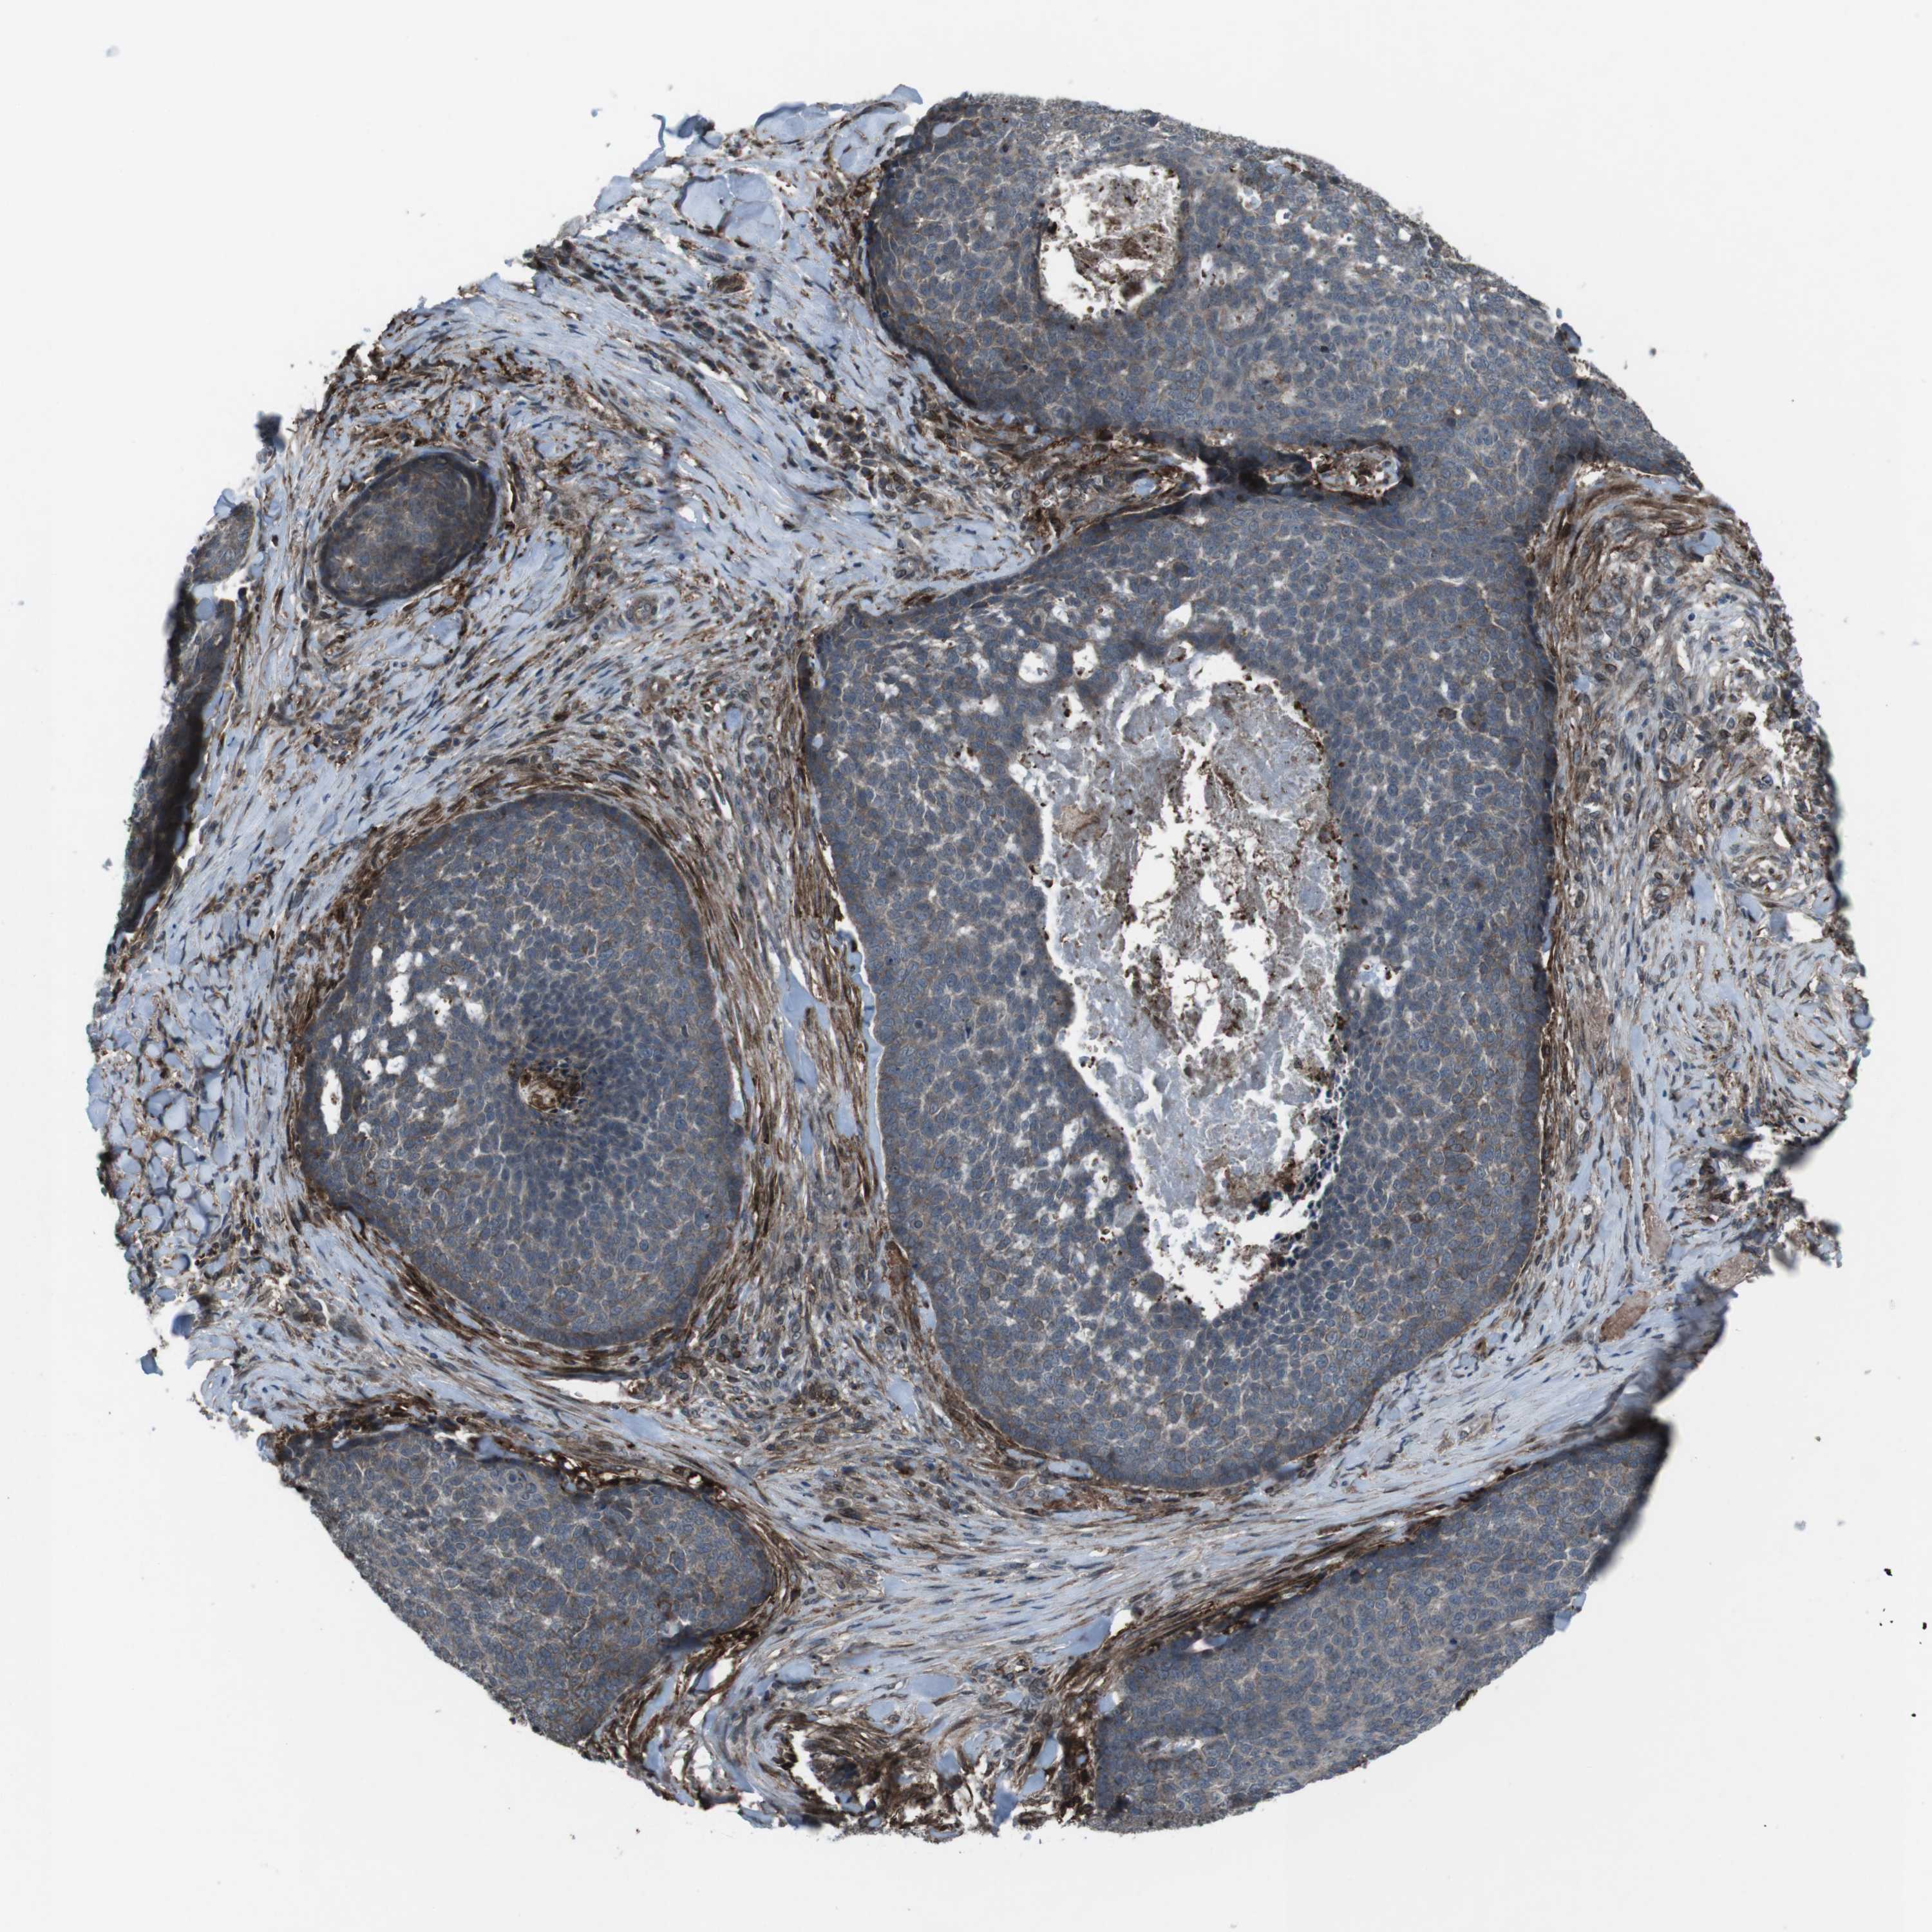

SKIN CANCER - Protein expressioni

A mouse-over function shows sample information and annotation data. Click on an image to view it in a full screen mode. Samples can be filtered based on level of antibody staining by selecting one or several of the following categories: high, medium, low and not detected. The assay and annotation is described here.

Antibody staining in the annotated cell types in the current human tissue is reported as not detected, low, medium, or high, based on conventional immunohistochemistry profiling in selected tissues. This score is based on the combination of the staining intensity and fraction of stained cells.

Each image is clickable and will lead to virtual microscopy that enables deeper exploration of all samples and also displays staining intensity scores, fraction scores and subcellular localization as well as patient and tissue information for each sample.

Antibody HPA015498

Staining

High

Medium

Low

Not detected

Intensity

Strong

Moderate

Weak

Negative

Quantity

>75%

75%-25%

<25%

None

Location

Nuclear

Cytoplasmic/membranous

Cytoplasmic/membranous,nuclear

Squamous cell carcinoma in situ, NOS

Squamous cell carcinoma, NOS

Basal cell carcinoma

Adnexal tumor, benign